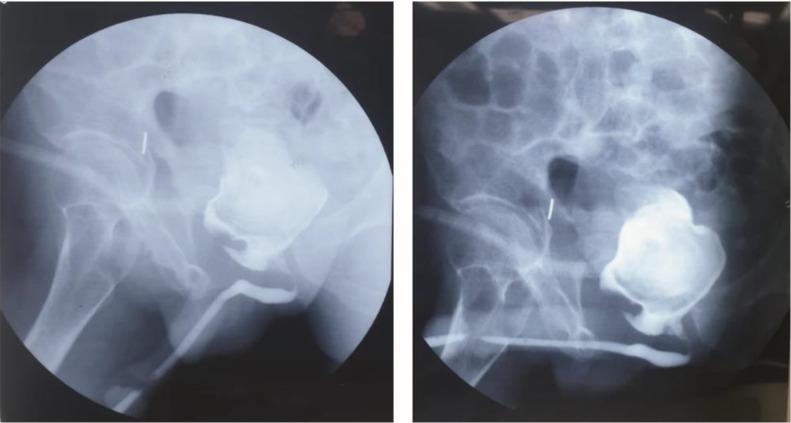

Giant bladder calculi are rare and long-term usage of cystostomy could cause stone formation. Due to the lack of evidence on giant bladder calculi and the long-term usage of cystostomy can cause bladder calculi formation, we provide a case study of a man with a neglected cystostomy with giant bladder calculi for 4 years. A fixed mass was discovered in the suprapubic region. Ultrasound examination revealed 4.1 × 5.5 cm bladder calculi and contracted left kidney. Bipolar voiding cystourethrography portrayed stricture in pars pendular and membranacea, uneven bladder wall, and 4.5 × 4.5 cm bladder calculi. The stone was extracted, and the bladder filling test revealed a small bladder capacity. Since the patient refused urethral reconstruction and bladder augmentation, he was discharged with another cystostomy catheter. Six-month follow-up revealed no forming stones. Neglected cystostomy catheter can cause giant bladder calculi. Prompt diagnosis and treatment should be made to manage this condition to reduce the likelihood of bladder cancer.

巨大膀胱结石较为罕见,长期使用膀胱造瘘术可能导致结石形成。鉴于缺乏关于巨大膀胱结石的证据,且长期使用膀胱造瘘术会导致膀胱结石形成,我们提供了一个病例研究,该患者因膀胱造瘘术被忽视,患有巨大膀胱结石达4年之久。在耻骨上区域发现一个固定肿块。超声检查显示有4.1×5.5厘米的膀胱结石以及左肾萎缩。双极排尿膀胱尿道造影显示尿道悬垂部和膜部狭窄、膀胱壁不平整以及4.5×4.5厘米的膀胱结石。结石被取出,膀胱充盈试验显示膀胱容量较小。由于患者拒绝尿道重建和膀胱扩大术,他带着另一根膀胱造瘘导管出院。六个月的随访显示无结石形成。被忽视的膀胱造瘘导管可导致巨大膀胱结石。应及时进行诊断和治疗以处理这种情况,从而降低患膀胱癌的可能性。